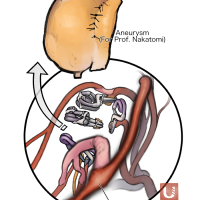

術後イラストシリーズ

監修:太田 仲郎